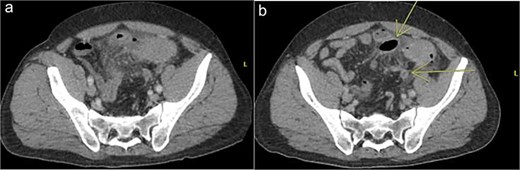

A 64 year old female with a history of recent diverticulitis treated with outpatient antibiotics and a fall two months prior to her left flank presented to the hospital with persistent left flank and abdominal pain. Initial workup showed a left flank fluid collection that connected to the left psoas muscle and retroperitoneum with associated descending/sigmoid diverticulosis (Fig. 1). The patient was admitted, started on empiric IV antibiotics, and an IR-guided drain was placed into the subcutaneous abscess. A repeat computed tomography (CT) scan done with rectal contrast showed a colocutaneous fistula to the descending/sigmoid colon in the area of the previous abscess. Therefore the patient was taken to the operating room on hospital day two. Intra-operatively, the patient was found to have purulent peritonitis, left colon diverticulitis, a colocutaneous fistula, and an associated pericolic abscess. The patient underwent extensive lysis of adhesions, take down of fistulous tract, and left colectomy with primary anastomosis. The fascia was closed with #1 non looped PDS and interrupted figure of eight stitches. The umbilicus was reapproximated with sutures and a negative pressure subcutaneous wound vac was placed to the midline laparotomy incision and kept on continuous suction at -125mmhg. The first wound vac change occurred on postoperative day (POD) 3 (Fig. 2a) and then the wound vac was changed every other day in the hospital until a layer of granulation tissue was formed along the entire incision. On POD 13, DPC was performed by reapproximating the skin edges with staples (Fig. 2b). The patient’s hospital course was complicated by a prolonged postoperative ileus requiring supplemental total parenteral nutrition (TPN). The patient was discharged to home on POD 13 tolerating a diet and with one week of oral antibiotics. The patient was then seen in the office 15 days after discharge and DPC on POD 28. The midline incision was closed, healing well, and was without any signs of SSI (Fig. 2c).

Patient A. Initial CT abdomen and pelvis showing left subcutaneous fluid collection extending intra-abdominally.